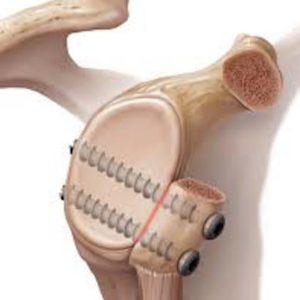

Botblok procedure

Na terugkerende ontwrichtingen naar achter na het uitvoeren van een hechting via kijkoperatie, bij botverlies na een ontwrichting naar achter of bij een terugkerende luxatie na een latarjet ingreep wordt een botblok geplaatst tegen de kom van de schouder.

Een stukje bot van 3x2cm wordt weggenomen ter hoogte van de bekkenkam en nadien vast geschroefd ter hoogte van het letsel van de kom. Op die manier wordt het oppervlak van de kom groter gemaakt.